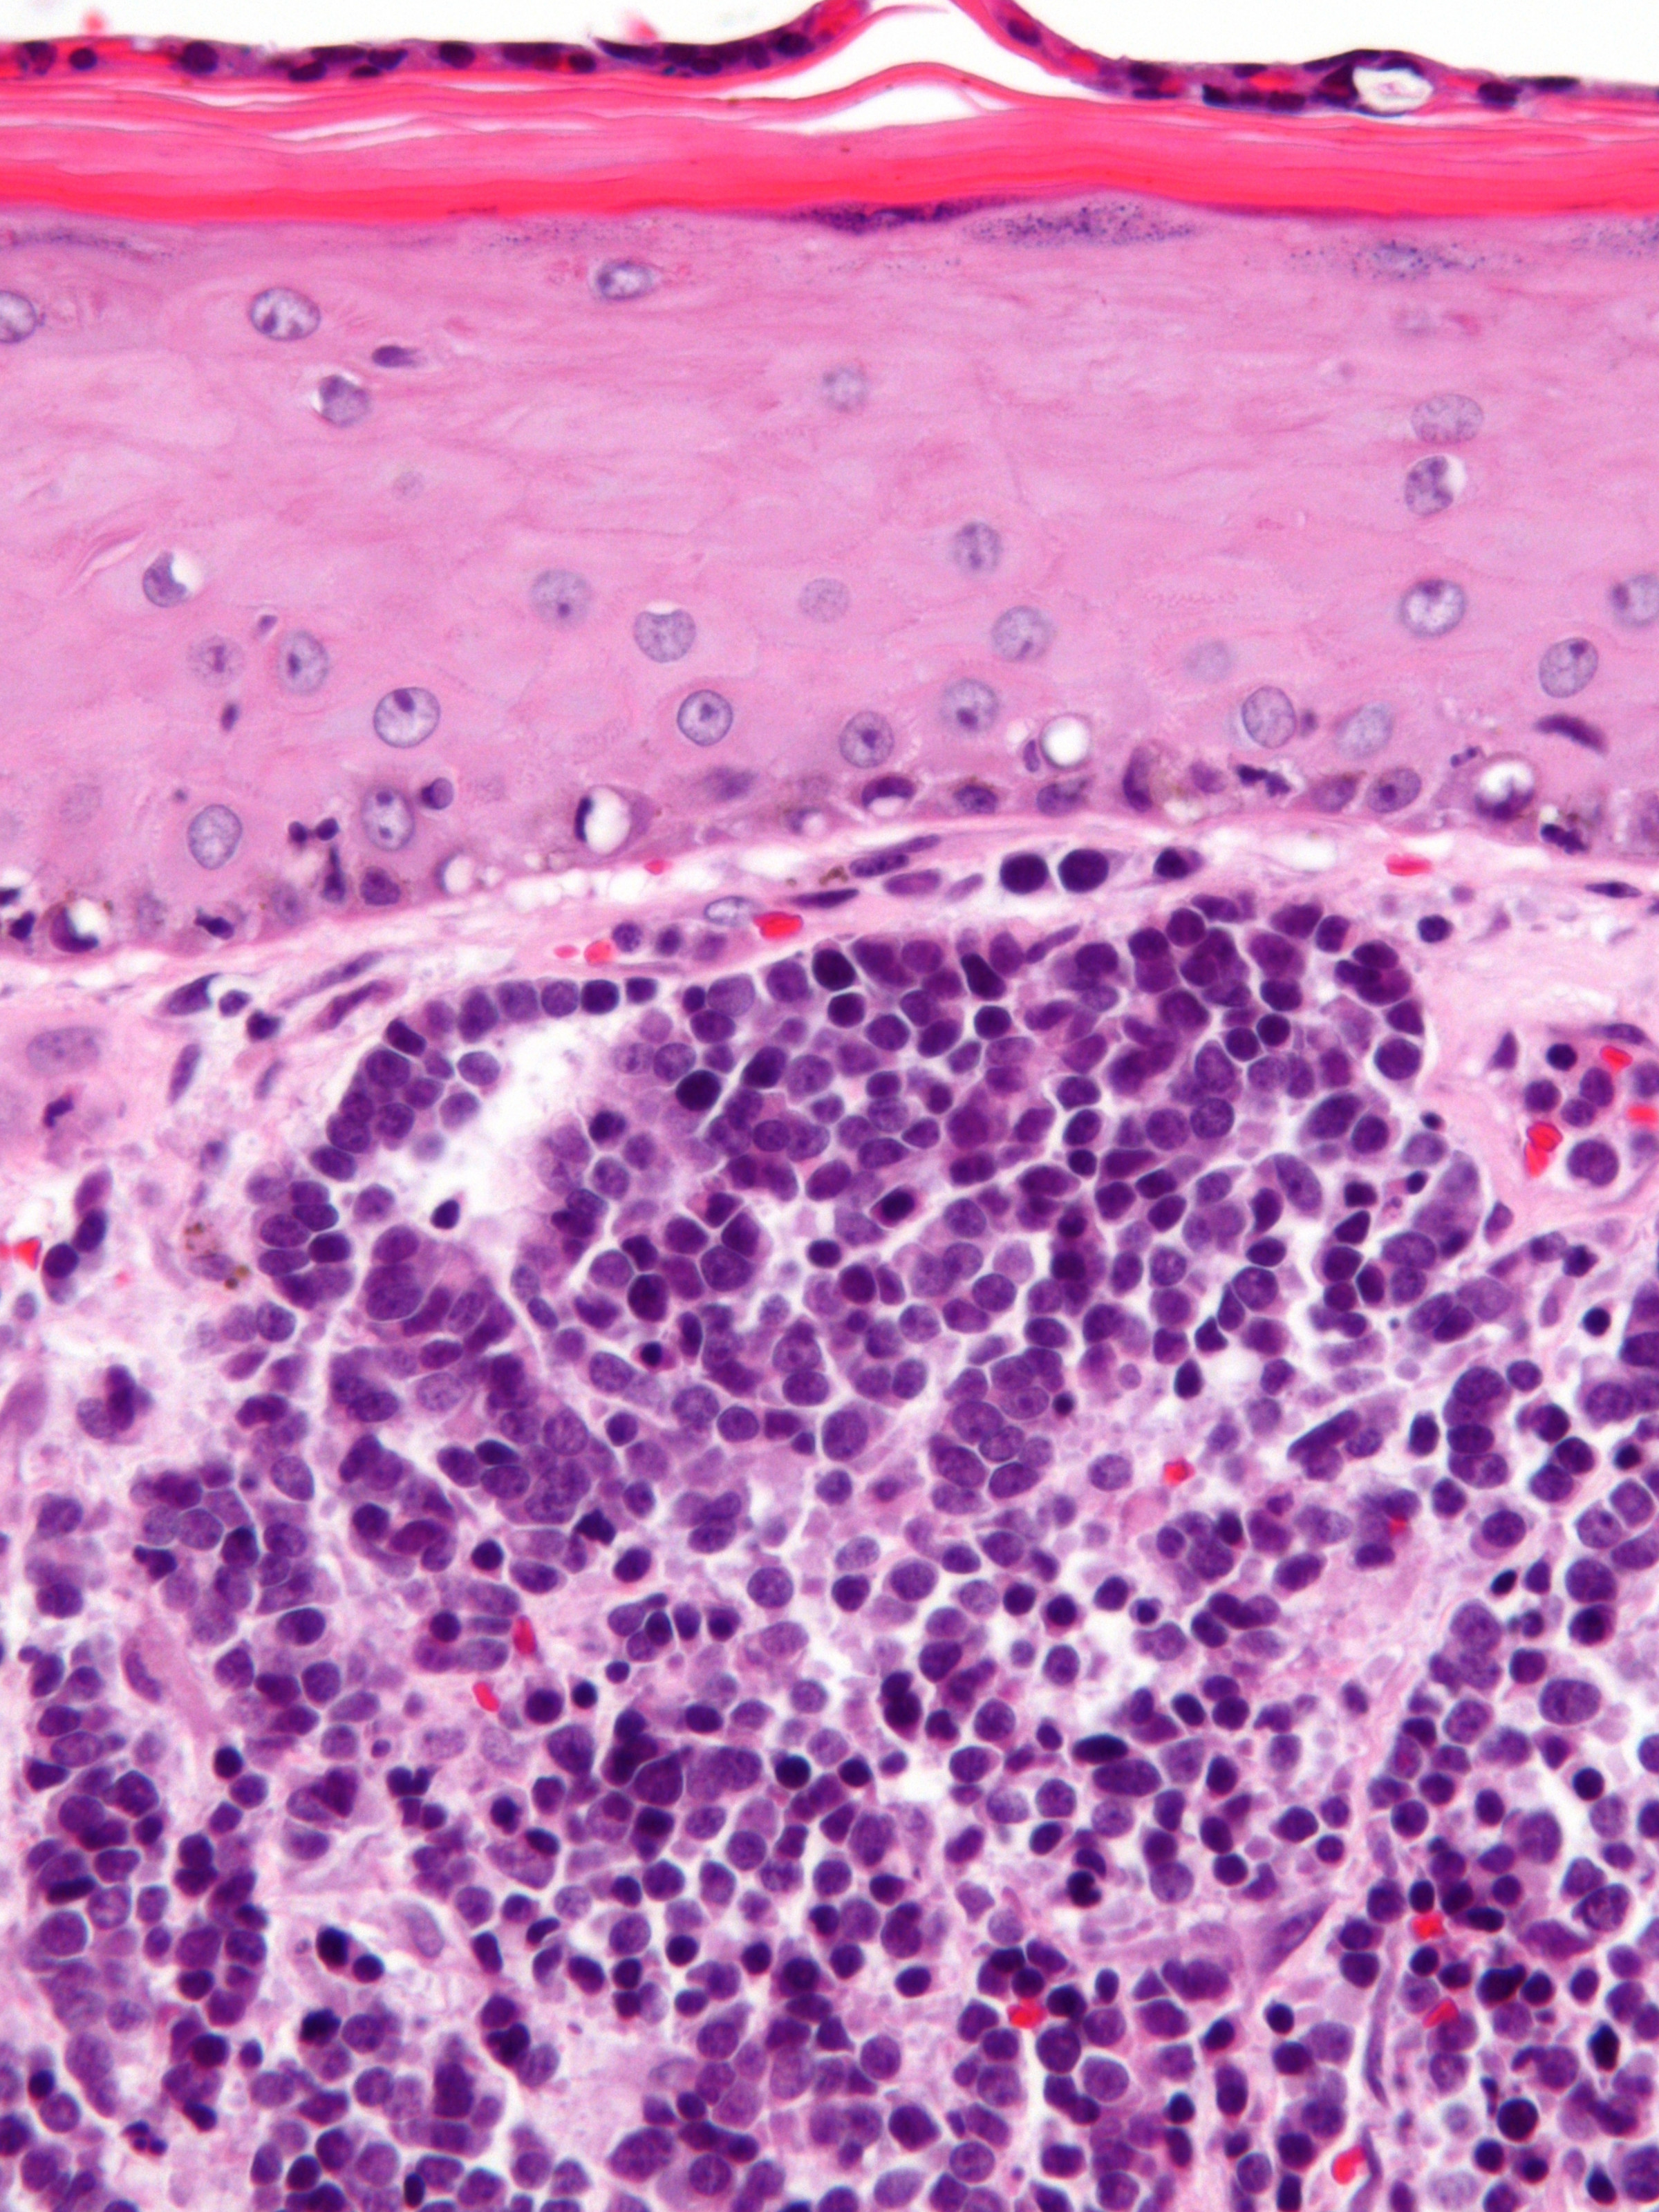

PA:

In de dermis, soms reikend tot in subcutis zijn velden van kleine ronde tumorcellen te zien (‘small blue round cells’). De tumorcellen zijn meestal gerangschikt in nesten, platen of strengen (trabekels). Soms worden ‘Homer-Wright pseudo-rosetten’ gezien, dat zijn kransen van tumorcellen rond een centrale zone gevuld met neurofibrillair materiaal, typerend voor neuro-endocriene tumoren. De tumorcellen zijn klein tot middelgroot en hebben zeer weinig cytoplasma en grote kernen t.o.v. de hoeveelheid cytoplasma. De celkernen vertonen een karakteristiek ‘salt and pepper’ chromatinepatroon (fijnkorrelig chromatine) met onopvallende nucleoli. Er zijn vele mitosen te zien. De tumor kleurt aan met cytokeratine 20 (CK20) en met neuro-endocriene markers (chromogranine A, synaptofysine, CD56). TTF (positief bij longcarcinoom) en S100 (positief bij melanoom) zijn negatief. Bij ongeveer 80% van de gevallen kan het Merkelcel-polyomavirus in de tumorcellen worden aangetoond.